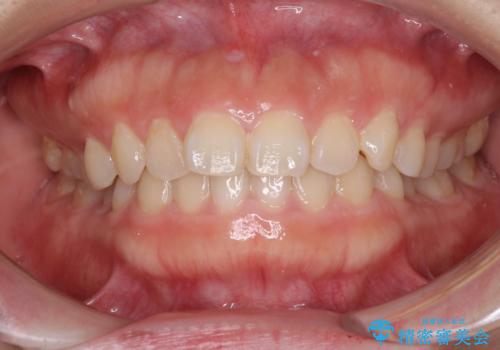

- 前歯のデコボコを治したいとのことで来院された患者様です。

上下顎ともに歯列全体の側方拡大とIPR(歯と歯の間を削る)によってデコボコが解消するように設計し、インビザラインにより治療を行うこととしました。

1日22時間の装着時間をしっかり守ってくださったので、1年程度で治療を終えることができました。

1セットのマウスピースで概ね治療を終えたのですが、前歯僅かな叢生が残ったため、2セット目のマウスピースで仕上げました。

気にしていた口元の印象が改善され、患者様には大変満足していただきました。